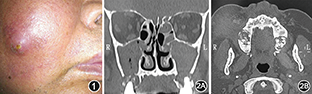

患者男,57岁,2012年7月因"牙龈天疱疮"就诊于我院皮肤科,给予甲泼尼龙片每日48 mg口服,逐渐减量为16 mg,同时口服阿仑膦酸钠,每日70 mg预防骨质疏松。2014年1月患者因右侧面部肿胀、疼痛,回吸吐出有臭味的黄色黏稠脓液2周就诊于我科,门诊诊断为"牙源性鼻窦炎",行"右侧颊龈部切开引流术",引流出黄色黏稠脓液,细菌培养结果为草绿色链球菌、奈瑟菌。口腔科建议耳鼻咽喉科先控制上颌窦内感染,患者遂于2014年1月14日收入我科。患者否认糖尿病病史。入院查体:面部肿胀,皮肤发红,皮温高,右侧面颊部皮肤菲薄几要破溃,质硬,按压疼痛(图1)。鼻中隔右偏,双侧总鼻道及中鼻道可见黄脓涕,双侧上颌窦压痛(+)。右上颌颊龈沟可见切开之瘘口,挤压可见脓液溢出。双侧颈部未触及肿大淋巴结。鼻窦CT:双侧上颌窦、筛窦、额窦内可见软组织密度影充填;双侧上颌窦开口堵塞,双侧上颌窦下壁及部分上颌骨骨质破坏吸收(图2),鼻中隔右偏。初步诊断:牙源性鼻窦炎、面部蜂窝织炎、鼻中隔偏曲。入院后第1天局麻下行内镜下双侧上颌窦脓液引流术。术中见左侧中鼻甲肥大,骨质增生,鼻中隔右偏,双侧中鼻道难以暴露。故行双侧下鼻道开窗术,探下鼻道外侧壁骨质明显增厚变硬,开窗器难以进入,遂以骨凿凿入上颌窦腔,其内大量脓液,用生理盐水冲洗窦腔。扩大右侧上颌颊龈沟瘘口,释放出大量脓液。患者右侧面部菲薄皮肤破溃,溢出大量脓液。脓液细菌培养及真菌镜检结果均为阴性。术后患者鼻部症状缓解,嘱其出院后口腔医院继续诊治。